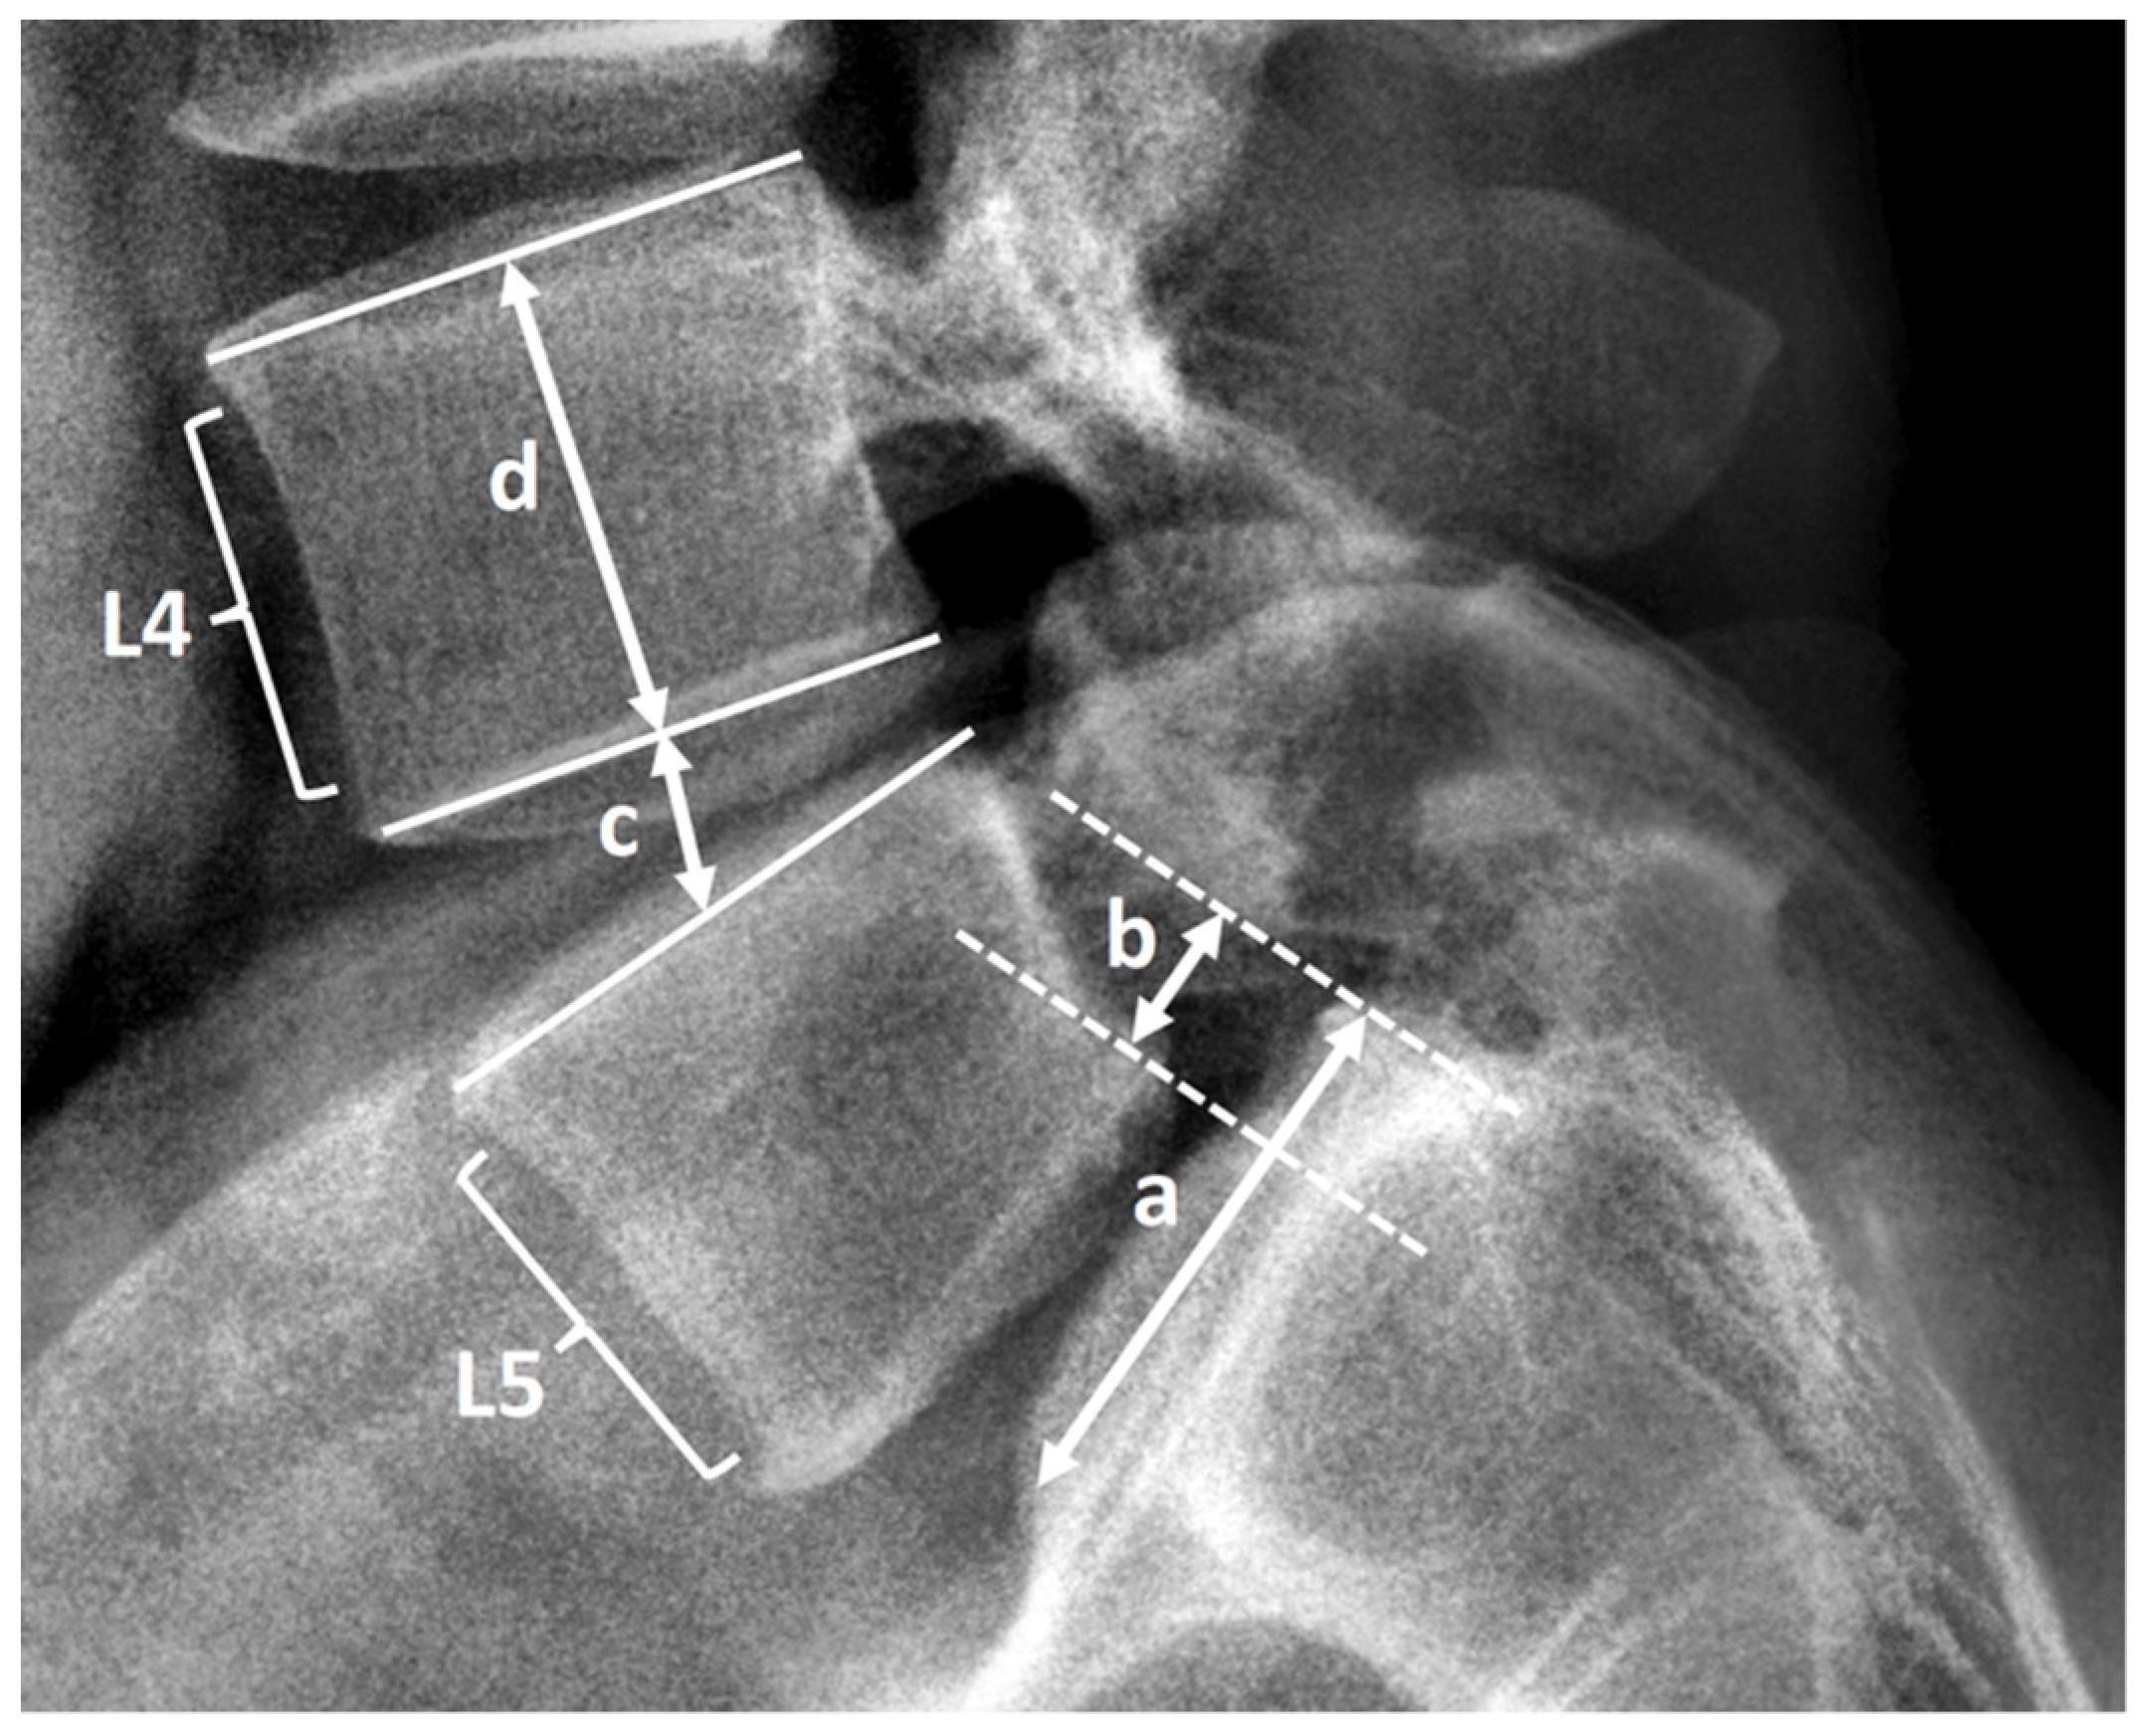

2.3. Radiological Assessment and Clinical Record